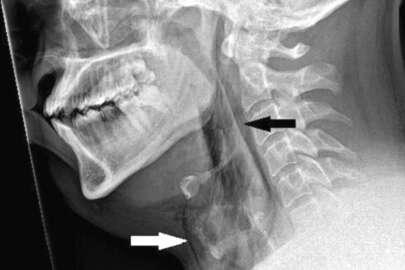

Yapılan taramalarda hastanın nefes borusunda 2 milimetrelik bir yırtık olduğu ortaya çıktı.